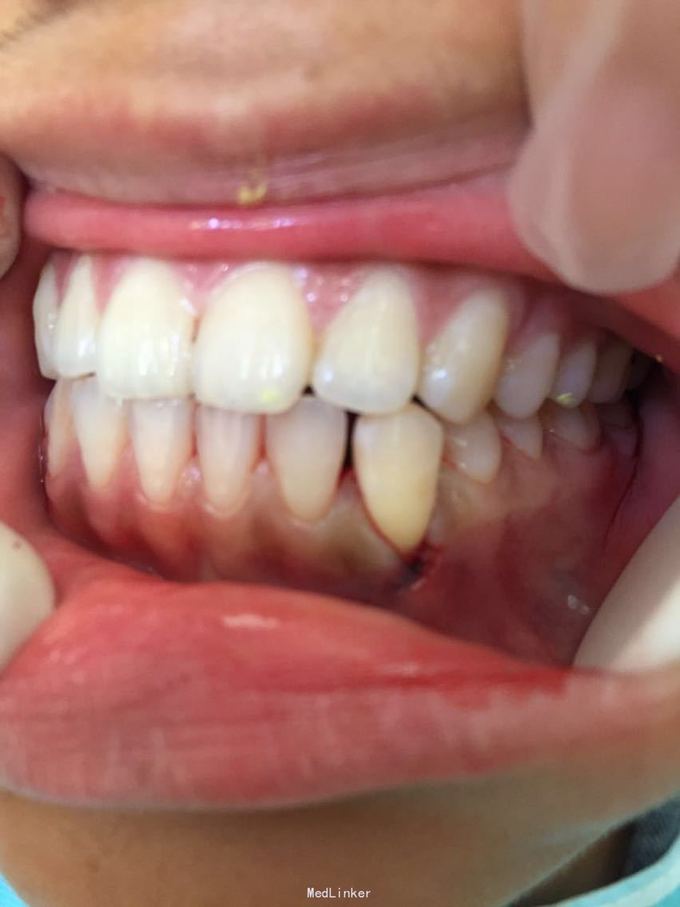

D3牙脱位 D3体外根管治疗后垫底充填,盐水和双氧水浸泡后,刮尽牙根的牙周膜后放置盐水和庆大霉素液中15分钟。局麻下刮除牙槽窝内血凝块至流鲜血后盐水和庆大霉素交替冲洗,明胶海绵拭干牙槽窝,浸泡好的牙体植入牙槽窝内并复位,舌侧树脂牙周夹板固定D123456,牙周上派丽奥。随诊